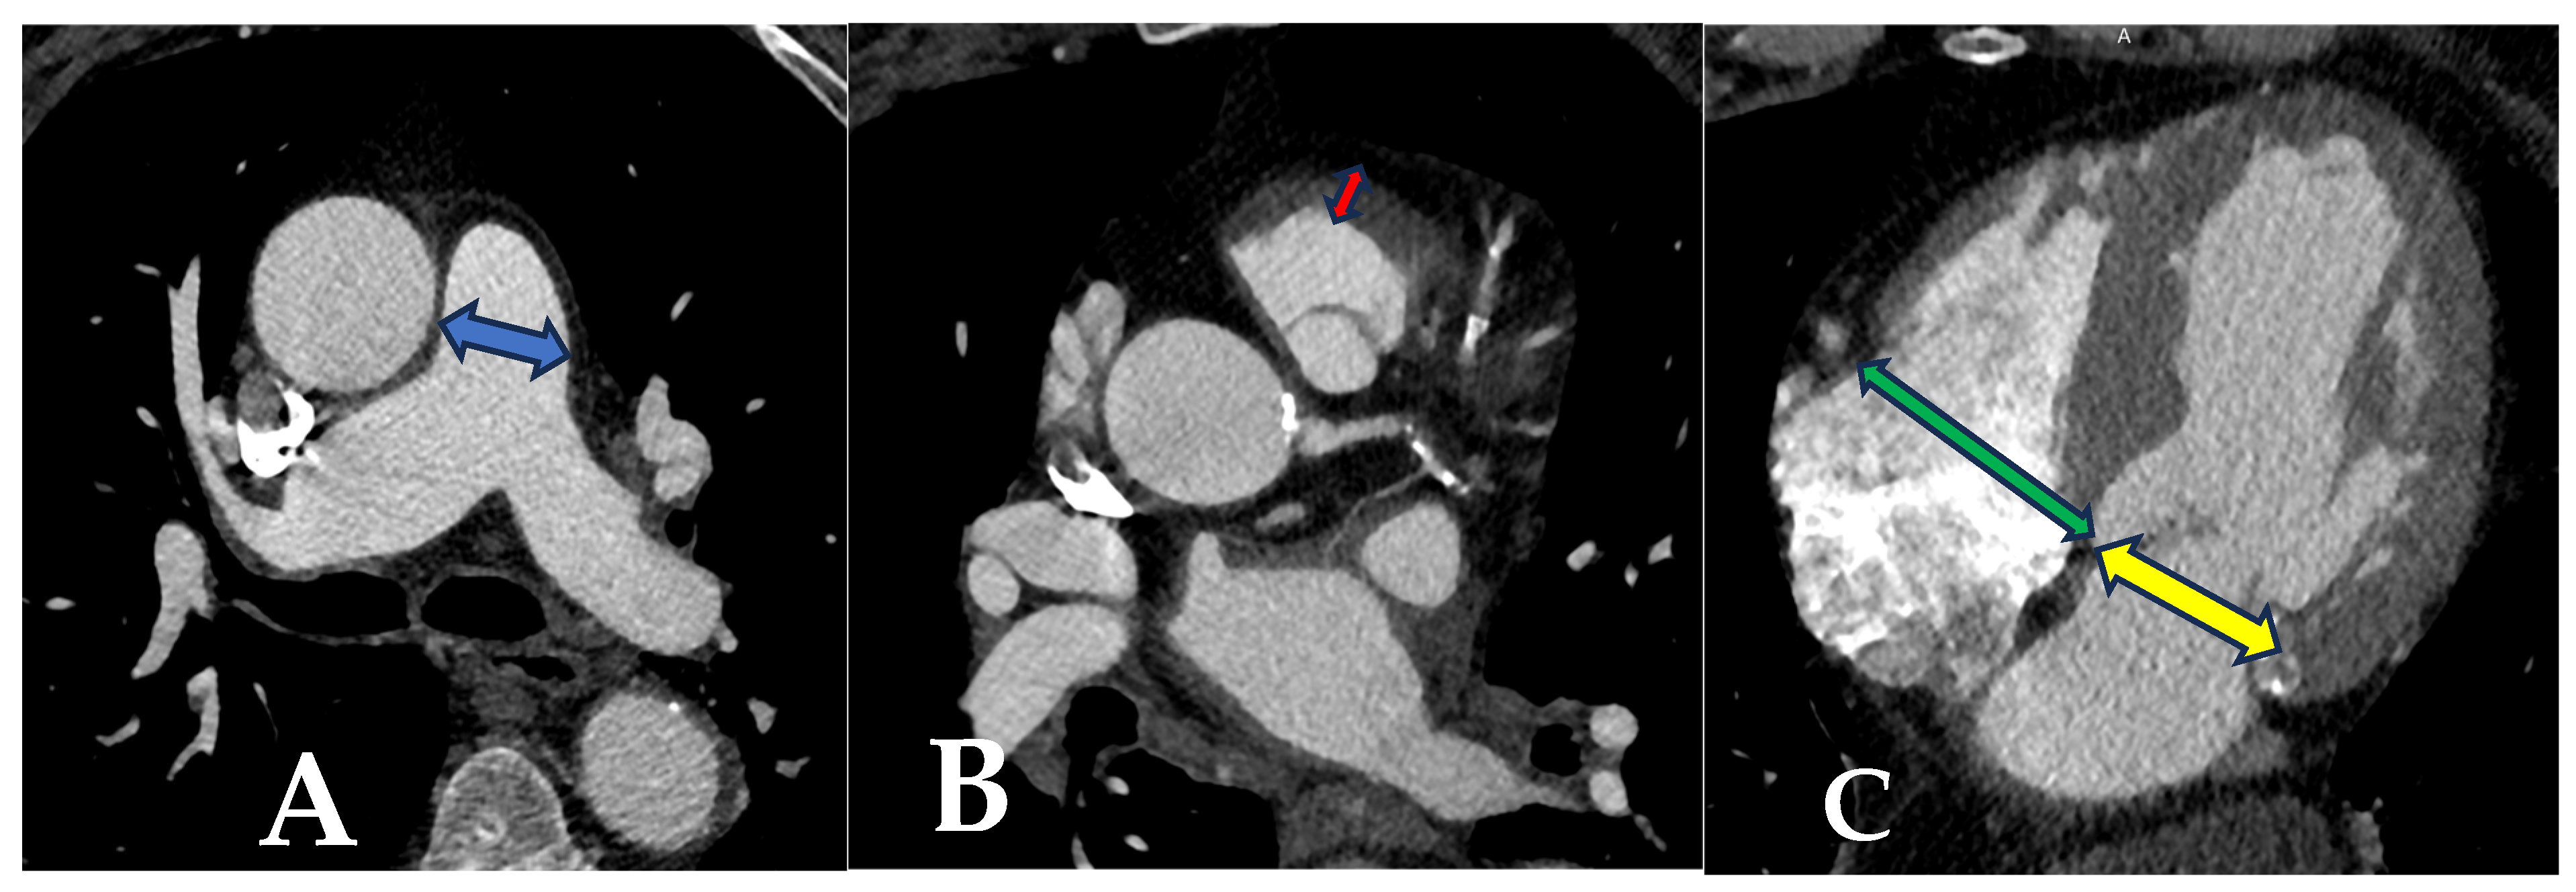

2.3. Tomographic Measurements

| PAD (mm) Median (IQR) | 25 (15–36) | 34.5 (28–43) | <0.001 |

| RVOTMT (mm) Median (IQR) | 3.5 (2.5–4.5) | 6,4 (4.9–7.2) | <0.001 |

| Maximal RVD/LVD Mean ± SD | 0.77 ± 0.12 | 1.15 ± 0.19 | <0.001 |